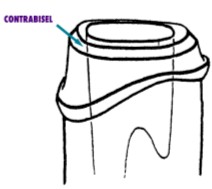

El efecto férula es definido como un collar

embargo ellos hablaban de un “contrabisel” (Fig. 13) preparado en el muñón

remanente, que al ser abrazado por el muñón falso, mantendría al diente unido,

como lo hacen los cinchos en un barril. No fue sino hasta 1990 en que

Sorensen describió todos y cada uno de los factores que deben ser tomados en

cuenta, y que son:

|

|

|

Fig. 13 |